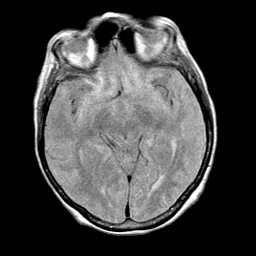

Pick's Disease, MR Study mr-pd -- Slice #9

[Home][Help][Clinical] Slice 9